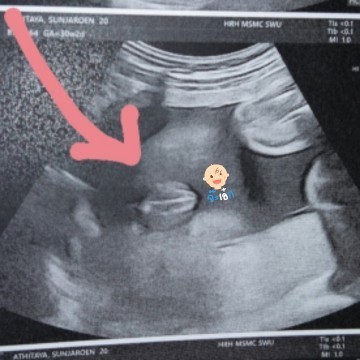

ช่วยดูหน่อยค่ะแม่ๆ กลีบใช่มั้ยคะ 😂😂

ชัดแต่กลัวไม่ชัวร์😂

เหมือนเป็นกลีบๆค่ะแม่

กำลังจะมีลูก